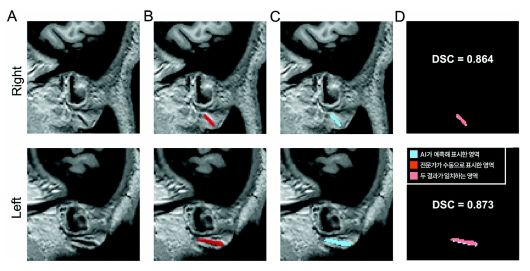

3차원 원본 이미지(A)를 토대로 전문가가 수동으로 직접 표시한 주름(B)과 AI가 예측해 자동으로 표시한 영역(C). |

분당서울대병원에서 수집한 뇌 MRI 400건을 바탕으로 전문가가 프랭크 징후를 수동으로 표시한 데이터를 AI에 학습시켰다. 이후 학습에 사용하지 않은 분당서울대병원 데이터 600건으로 1차 검증을 진행했고, 충남대병원·강원대병원·세브란스병원 등 다기관 데이터 460건으로 2차 검증을 실시했다.

검증에서는 전문가가 표시한 주름 영역과 AI가 자동으로 분할한 영역의 일치 정도를 비교했다. 그 결과 두 영역의 유사도를 나타내는 DSC(Dice 유사도 계수) 값은 각각 0.734와 0.714로 나타났다. 의료 영상 분야에서 0.7 이상은 높은 정확도로 평가된다. 프랭크 징후의 유무를 구분하는 성능을 나타내는 AUC(곡선 아래 면적) 값 역시 모두 0.9 이상을 기록해 다양한 임상 환경에서도 안정적으로 작동할 수 있음을 입증했다.